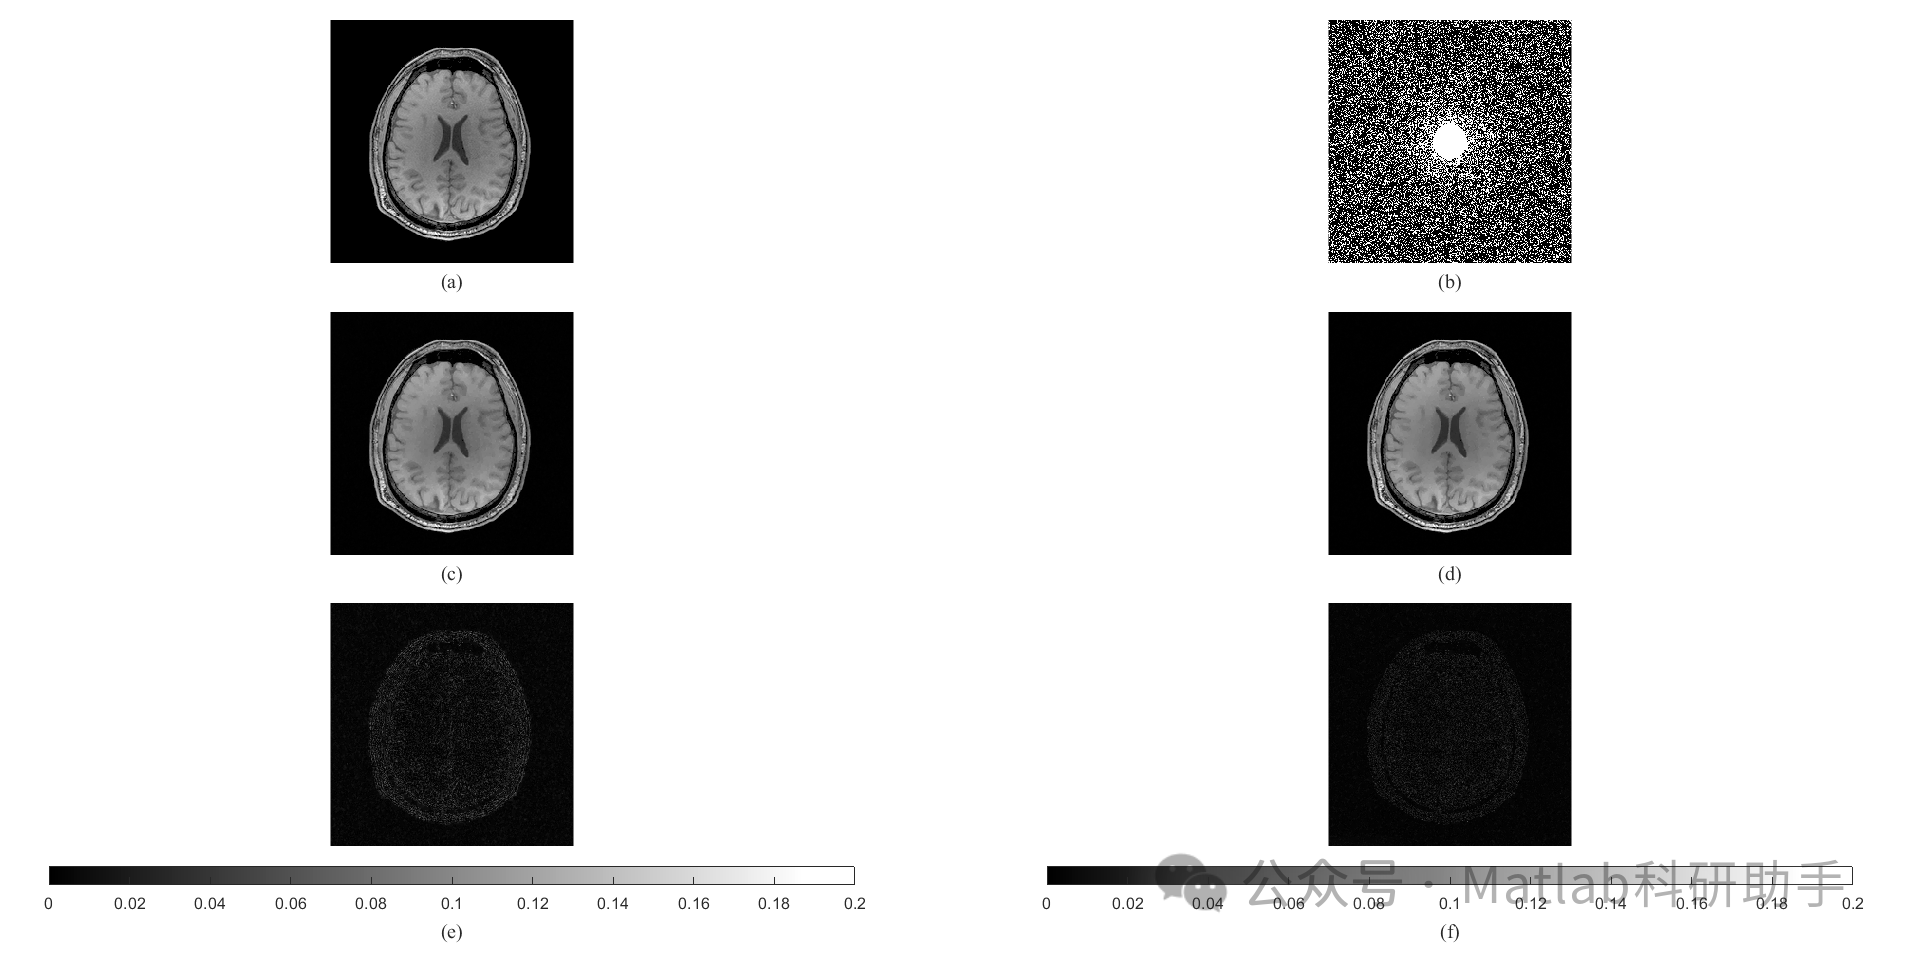

⛳️ 运行结果

与现有重建方法的比较: 为了验证 NCTV 方法的有效性,我们将与现有的 MRI 重建方法,例如,凸 TV 方法、Wavelet 方法等,进行比较分析。 通过对重建图像的视觉效果和量化指标 (例如,峰值信噪比 (PSNR)、结构相似性指数 (SSIM) 等) 的比较,来评估 NCTV 方法的性能。